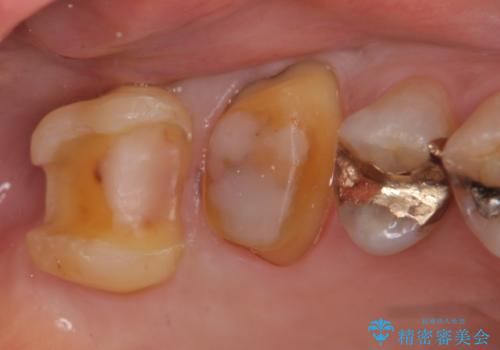

右上6,7の金歯を外したところ、虫歯が歯茎より深い位置まで進行していたため歯周外科を行いました。

その後歯茎の回復を待ち、オールセラミッククラウンおよびセラミックインレーによる補綴・修復を行いました。

虫歯が進み歯茎より深くなってしまうと、虫歯を取り残してしまうリスク、樹脂の硬化の妨げ、補綴物の不適合、歯肉炎・歯周病のリスクの増大等様々な弊害が起こり得ます。

そのため当院では歯周外科手術(歯茎を下げる手術)や歯の挺出による、虫歯が歯茎より深いという問題の解決を推奨しております。